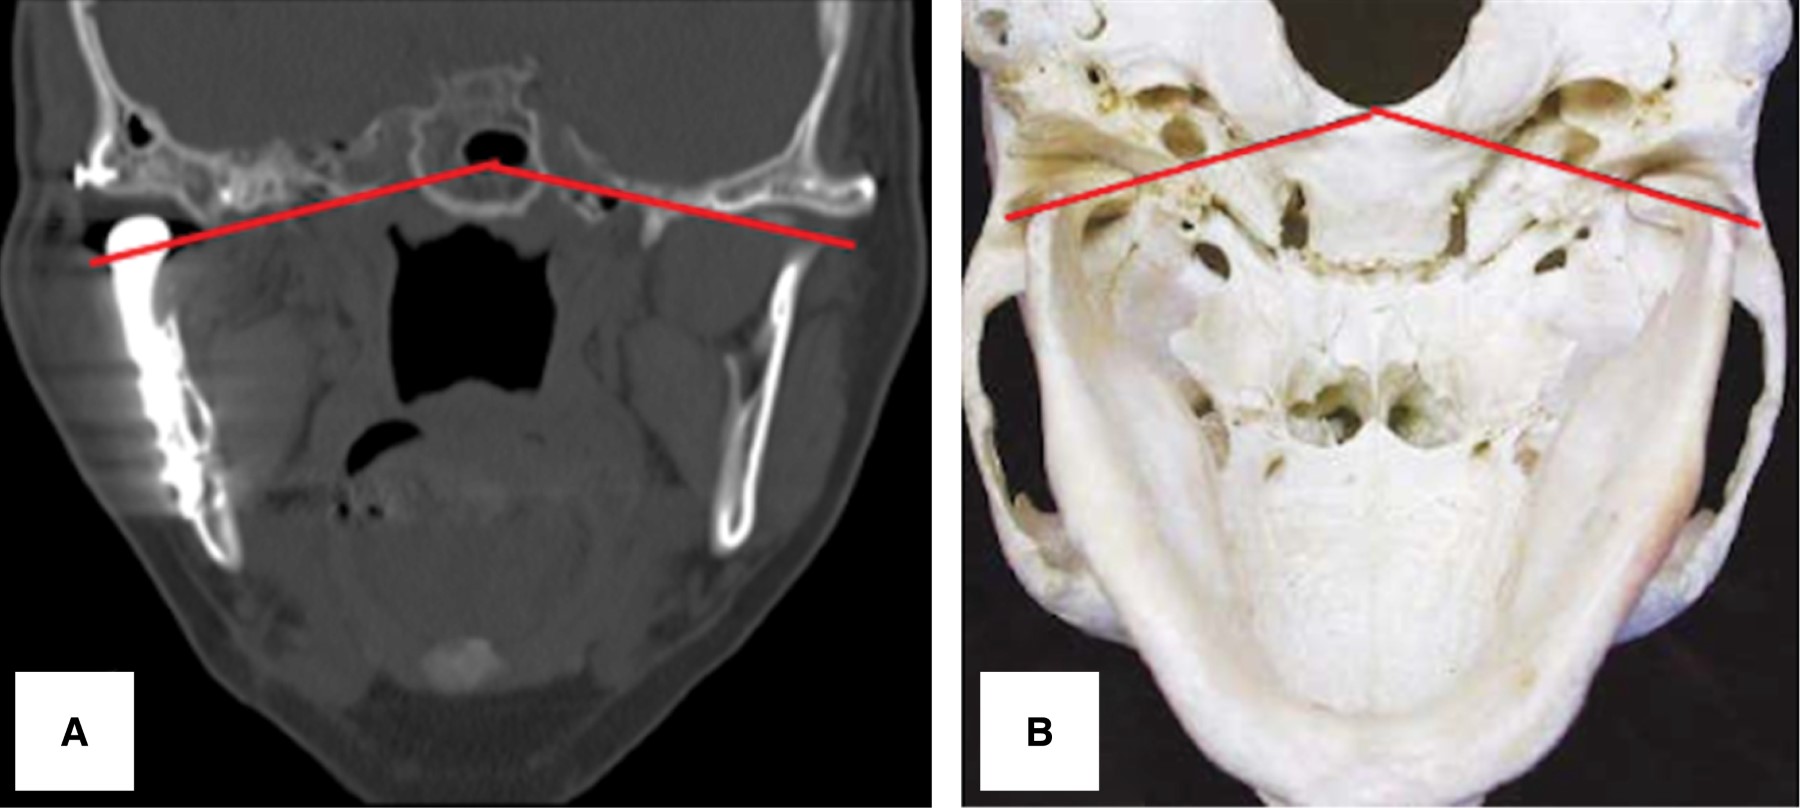

La paciente del caso 1 posterior a la cirugía presento 20 milímetros de apertura bucal, iniciando fisioterapia forzada al día siguiente del RTATM y durante seis meses más. Incluso ella refiere continuar con los mismos de manera ocasional por iniciativa propia. Actualmente con un seguimiento a cinco años no hay evidencia de reanquilosis, presentando una apertura de 35 mm (Figura 7 A y B), con movimientos mandibulares protrusivos y laterales y oclusión estable. La comparación de una corte coronal de una vista inferior del cráneo mostró simetría de las articulaciones temporomandibulares (Figura 8 A y B).